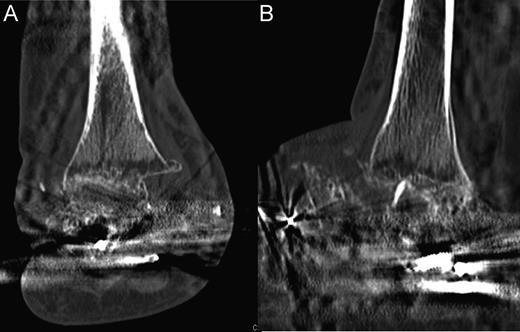

After having the external fixation for 8 months in total, it was removed when fusion was deemed adequate on computed tomography imaging (Fig. 5). She was instructed to weight bear while in a plaster of paris cast for 14 days and then a moon boot for 14 days. Two months after this, the patient was mobilizing without issues and was doing well. At 12 months, the patient stated that she is able to mobilize with any mild residual pain controlled with analgesia.

Computed tomography scans illustrating tibiocalcaneal fusion 1 year postoperatively. (A) Anterior–posterior view; (B) Lateral view.